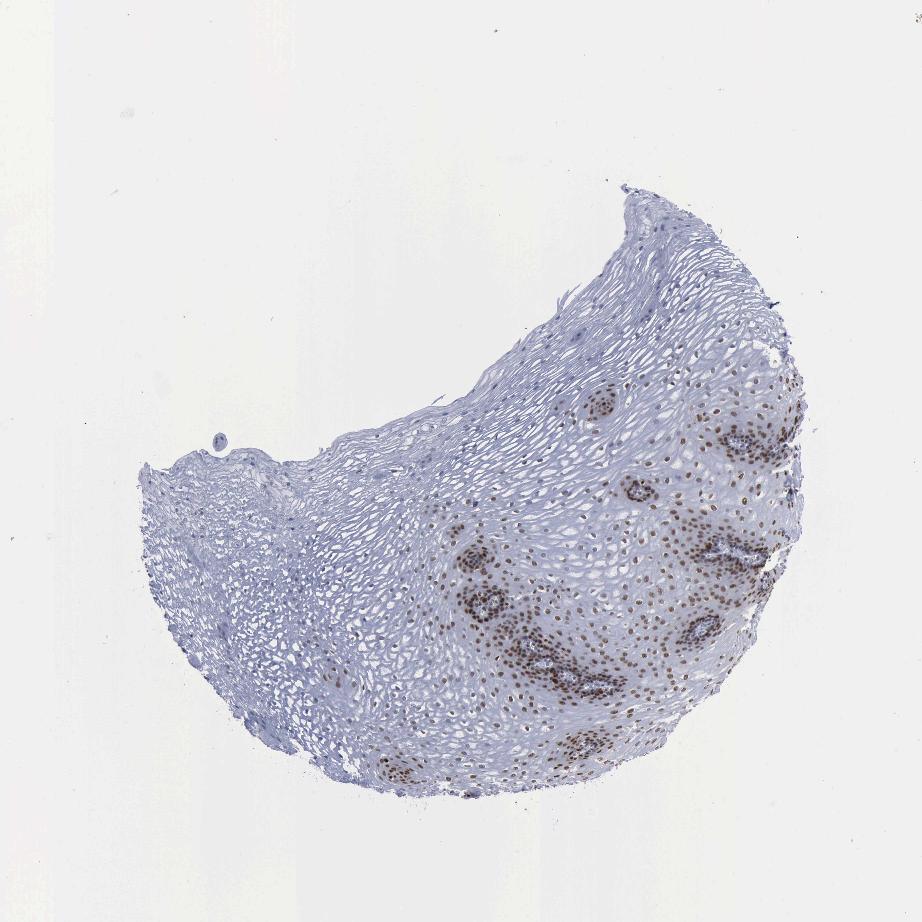

ESOPHAGUS - Antibody stainingi

Antibody staining in the annotated cell types in the current human tissue is reported as not detected, low, medium, or high, based on conventional immunohistochemistry profiling in selected tissues. This score is based on the combination of the staining intensity and fraction of stained cells.

Each image is clickable and will lead to virtual microscopy that enables deeper exploration of all samples and also displays staining intensity scores, fraction scores and subcellular localization as well as patient and tissue information for each sample.

Antibody HPA030521Antibody HPA030522Antibody HPA030523Antibody CAB000148Antibody CAB080240Antibody CAB080241Antibody CAB080242

Squamous epithelial cells HighHighMediumMediumHighHighHigh